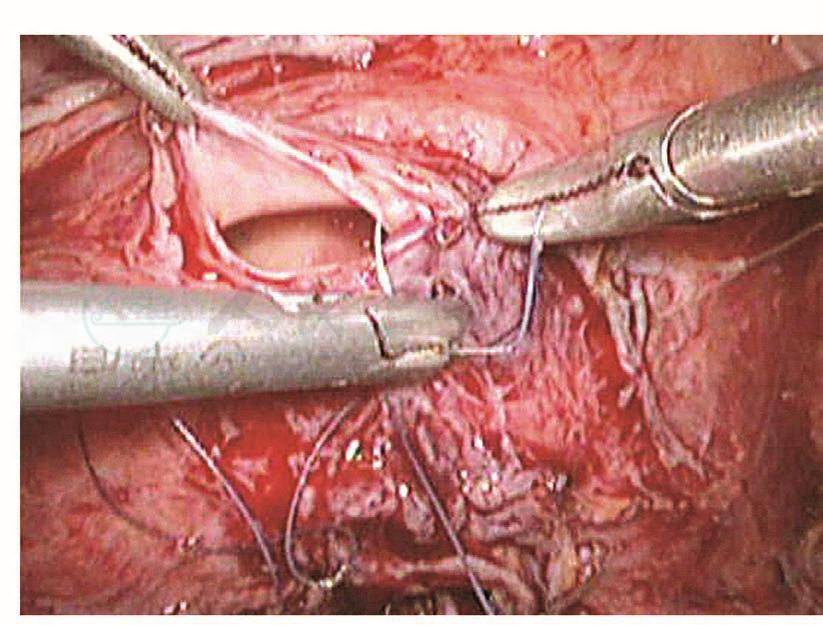

如果损伤长度>5mm,则需要手术处理。以往是先行暂时性肾盂造瘘下修补:根据笔者经验,如果术后15天内发现损伤,则可以直接采用腹腔镜下修补,可以减轻患者痛苦,缩短住院时间。该方法最关键的步骤是游离粘连的输尿管,因为,术后15天内组织开始出现明显的组织粘连。术前必须与患者及家属沟通并征得泌尿外科大夫同意后才进行手术。操作时,腹腔镜下探查盆腔,明确粘连程度及输尿管走向,分离粘连组织,暴露损伤的输尿管创面,从膀胱镜下插入导管,对合损伤面,用4-0的可吸收线在输尿管前、左、右三个方位各穿合一针。缝合时缝针从损伤口远端输尿管浆肌层进针,穿过黏膜层,再从近端黏膜层进针,穿出浆肌层,拉紧穿线,镜下打结。修补损伤面后,在膀胱镜下取出导管,再插入输尿管镜,明确输尿管通畅。然后,通过输尿管镜放进双J型支架,床边X线机明确双J管的位置,盆腔放置引流管,如果引流不多,48小时后取出。术后3个月在膀胱镜下取出双J管(图111~图116)。

图111 明确输尿管损伤部位

图112 游离输尿管

图113 将导管送进输尿管

图114 吻合输尿管

图115 修复后的输尿管

图116 放置引流管